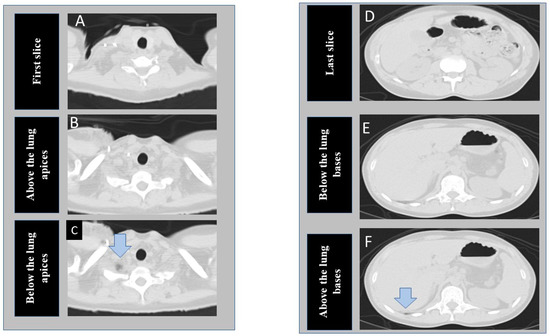

Radiologist-Trained and -Tested (R2.2.4) Deep Learning Models for Identifying Anatomical Landmarks in Chest CT

(1) Background: Optimal anatomic coverage is important for radiation-dose optimization. We trained and tested (R2.2.4) two (R3-2) deep learning (DL) algorithms on a machine vision tool library platform (Cognex Vision Pro Deep Learning software) to recognize anatomic landmarks and classify chest CT as those with optimum, under-scanned, or over-scanned scan length. (2) Methods: To test our hypothesis, we performed a study with 428 consecutive chest CT examinations (mean age 70 ± 14 years; male:female 190:238) performed at one of the four hospitals. CT examinations from two hospitals were used to train the DL classification algorithms to identify lung apices and bases. The developed algorithms were then tested on the data from the remaining two hospitals. For each CT, we recorded the scan lengths above and below the lung apices and bases. Model performance was assessed with receiver operating characteristics (ROC) analysis. (3) Results: The two DL models for lung apex and bases had high sensitivity, specificity, accuracy, and areas under the curve (AUC) for identifying under-scanning (100%, 99%, 99%, and 0.999 (95% CI 0.996–1.000)) and over-scanning (99%, 99%, 99%, and 0.998 (95%CI 0.992–1.000)). (4) Conclusions: Our DL models can accurately identify markers for missing anatomic coverage and over-scanning in chest CTs. Full article

Figure 1